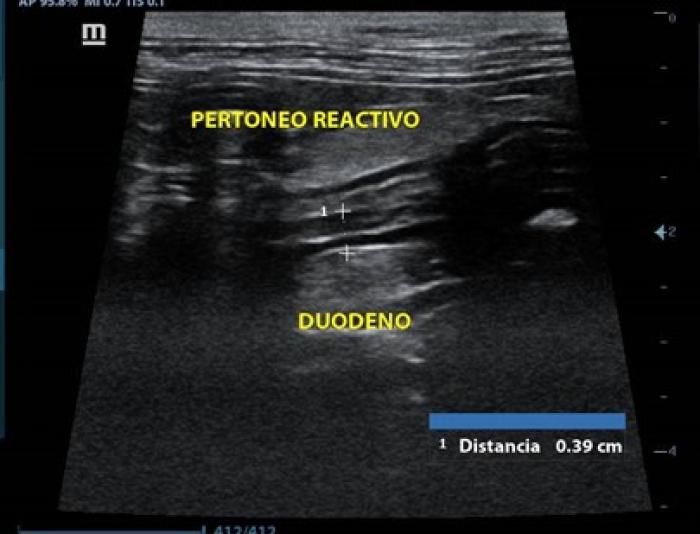

Química sanguínea: urea disminuida (5.6 mmol/l),los demás analitos dentro de rangos normales, hemograma sin alteraciones. Ultrasonido abdominal con ayuno de 8 h en el cual se observó estómago con presencia de gas, engrosamiento de segmentos duodenal (0.39 cm) (Figura10)y yeyunal (0.30-0.31 cm), el yeyuno con pérdida de definición de capas, así como la presencia de linfonodos yeyunales reactivos, con grasa perinodal hiperecoica y peritoneo reactivo adyacente al yeyuno (Figura11),vesícula biliar con presencia de sedimento biliar en cantidad moderada.

Los signos clínicos, así como los hallazgos que suelen observarse en el ultrasonido abdominal tales como aumento en el grosor de las capas intestinales, pérdida de definición de las capas, linfadenopatía reactiva y peritoneo hiperecoico son comunes para ambas enfermedades, por lo que en ningún caso se debe emitir un diagnóstico por este método ni basado en signología clínica. El promedio de las mediciones de la pared intestinal de ambos gatos superaron los 0.28 cm, por lo cual se justificaron la toma de las biopsias. La prueba gold standard para la diferenciación de las enteropatías crónicas felinas es el examen histopatológico de muestras de biopsias teñidas con H&E5.